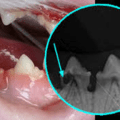

Tann- og tannkjøttsykdommer

Tannresorpsjon Hva er TR? Symptomer Arvelighet Behandling Forebygging Gingivitt, periodontitt, stomatitt Symptomer Arvelighet Behandling Tannproblemer hos katt er dessverre vanligere enn man skulle tro. Det er mange katteeiere som tror at det er normalt at katten mister en og annen… Les mer ›